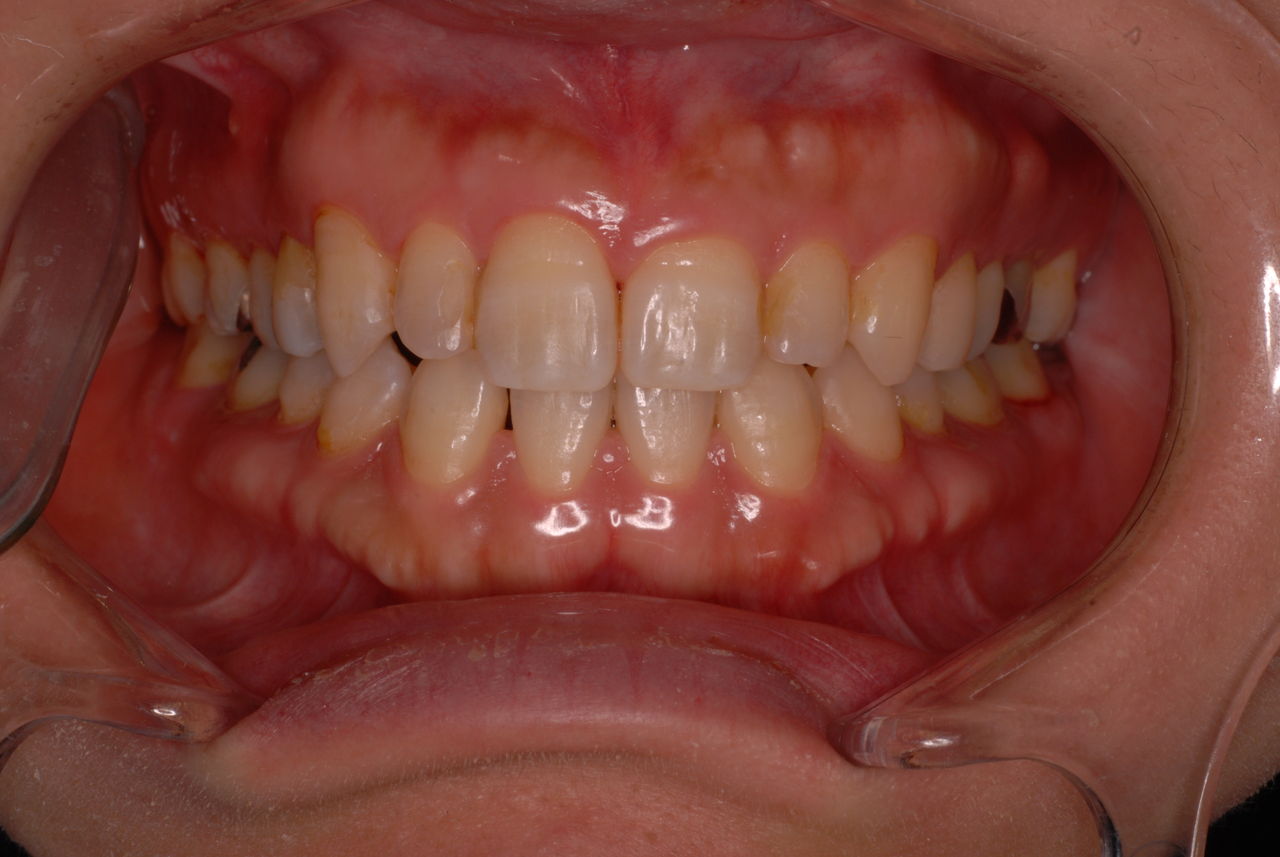

30代の男性の方です。

入れ歯を入れていました。歯科医院で歯を抜けず仕方なく入れ歯にしたとか。何とかならないものだったのか悔やまれました。

抜いた歯はありません。

一応差し歯にしましたが、歯茎の状態はよくはありません。

とりあえず希望を入れて差し歯にしたような感じです。